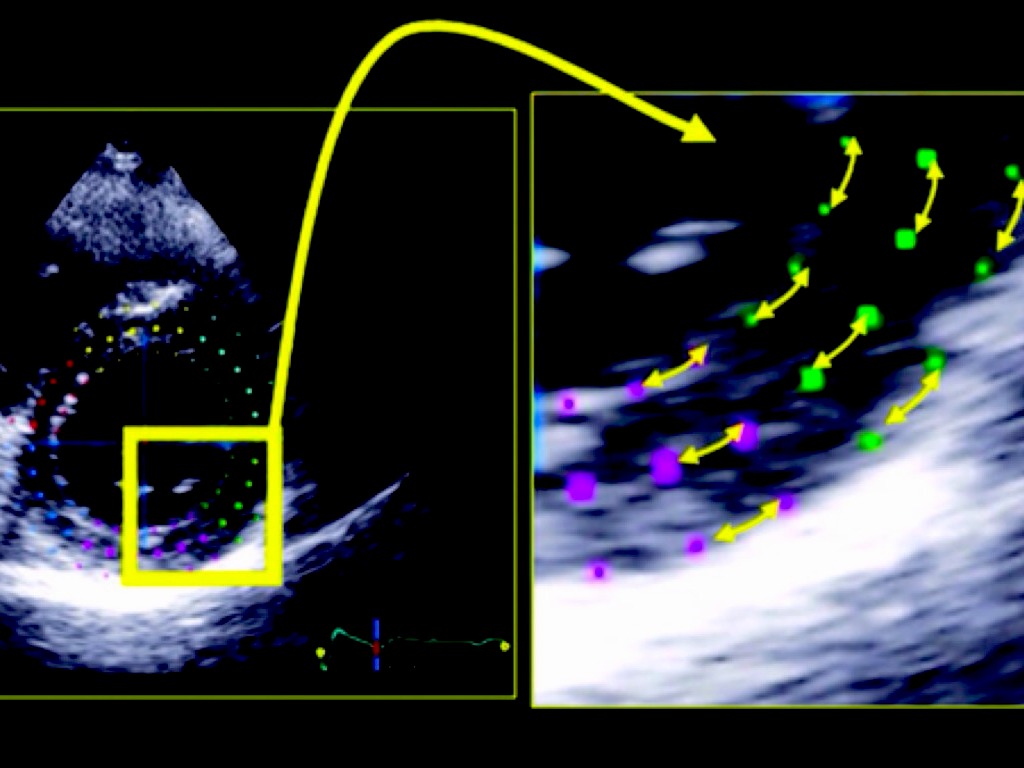

APLICAÇÃO DO STRAIN E STRAIN RATE NO DIAGNÓSTICO E MANEJO DA MIOCARDIOPATIA ISQUÊMICA

Georgia Rocha - MTDIC 4ª EDIÇÃO - Fev. 2014